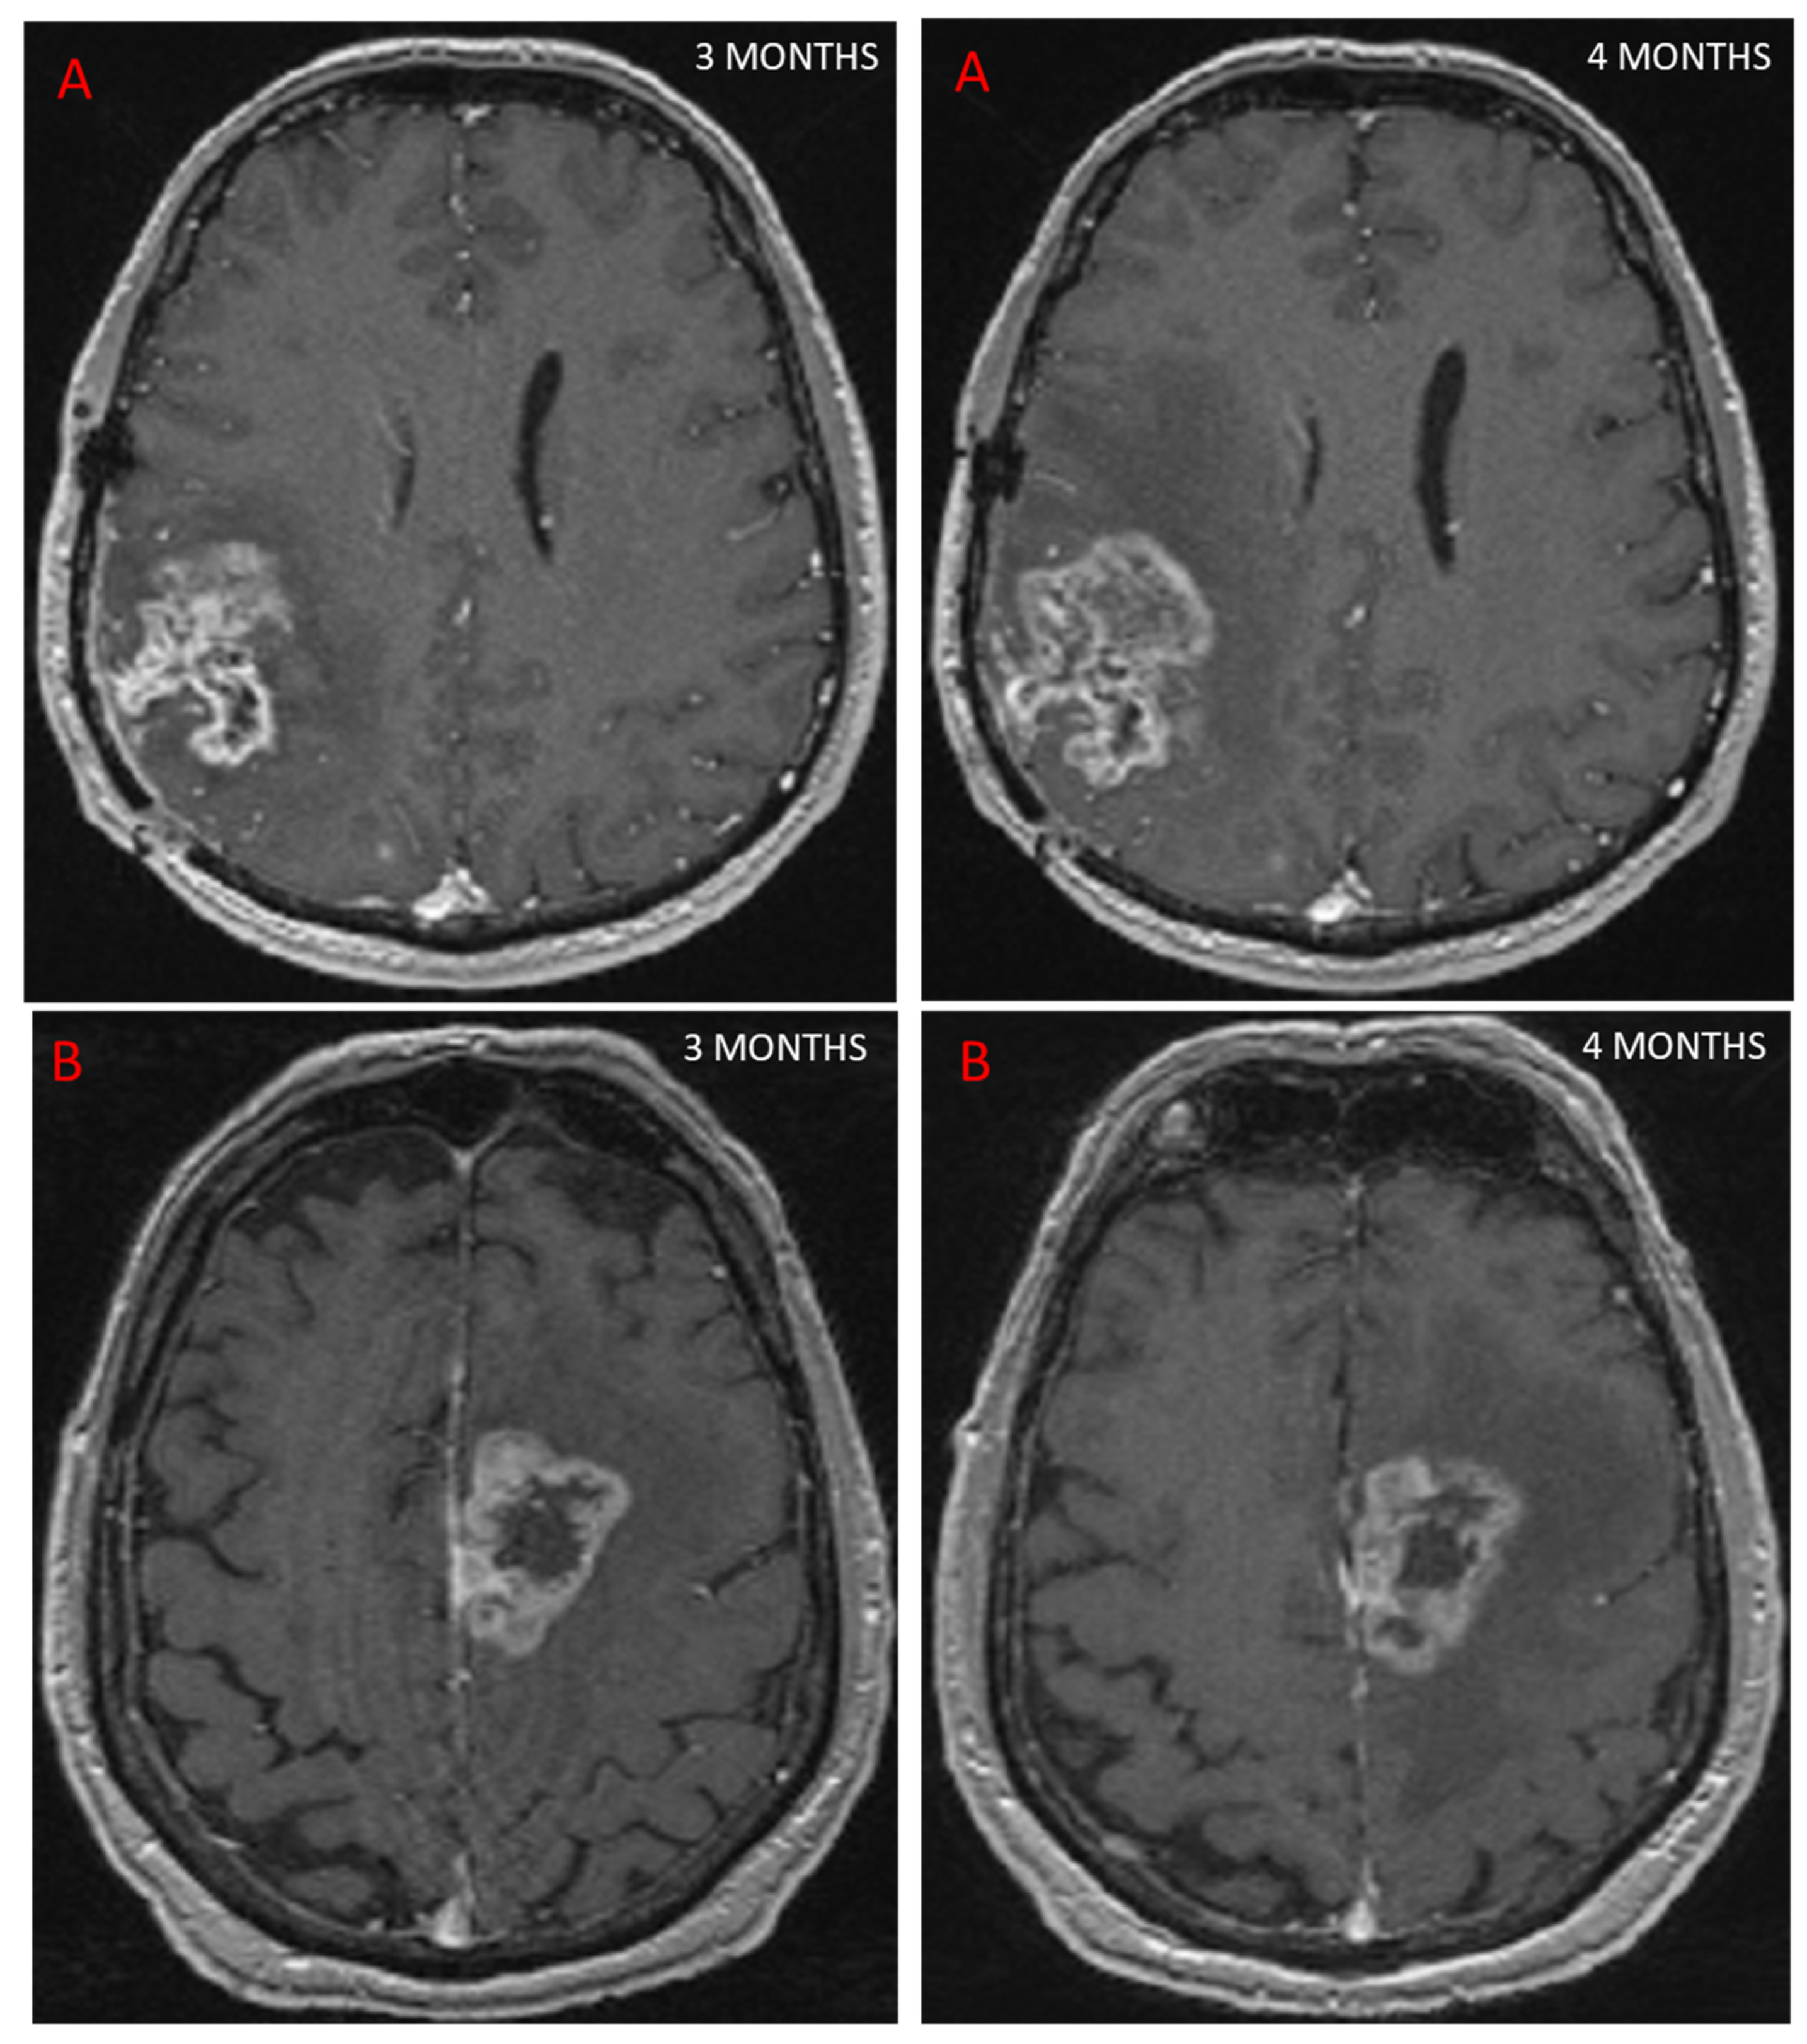

- Le Fèvre, C.; Constans, J.-M.; Chambrelant, I.; Antoni, D.; Bund, C.; Leroy-Freschini, B.; Schott, R.; Cebula, H.; Noël, G. Pseudoprogression versus True Progression in Glioblastoma Patients: A Multiapproach Literature Review. Part 2—Radiological Features and Metric Markers. Crit. Rev. Oncol. Hematol. 2021, 159, 103230. [Google Scholar] [CrossRef]